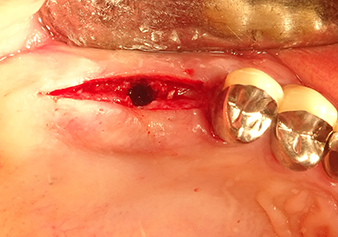

Una paziente di 49 anni, non fumatrice e con un'anamnesi priva di elementi rilevanti, è stata indirizzata al nostro studio di chirurgia orale per l'estrazione chirurgica del dente 16 ed il successivo impianto. Dopo l'estrazione, la paziente ha accusato dei lievi dolori causati dalla sinusite, motivo per cui abbiamo inizialmente aspettato sei mesi prima di procedere con l'intervento. L'altezza ossea residua in corrispondenza della posizione dell'impianto misurava 3-4 mm (Fig. 1 e 2).

Sono gli strumenti a svolgere il lavoro

Dopo la preparazione atraumatica del lembo mucoperiosteo, con l'ausilio dello strumento I1 è stata contrassegnata la posizione e preparata la sede dell'impianto fino ad avvertire la resistenza iniziale. Gli strumenti piezochirurgici sono stati utilizzati eseguendo un movimento verticale ascendente e discendente senza dover esercitare alcuna pressione. La vibrazione piezoelettrica ha generato la cavitazione richiesta ad elevata efficienza.